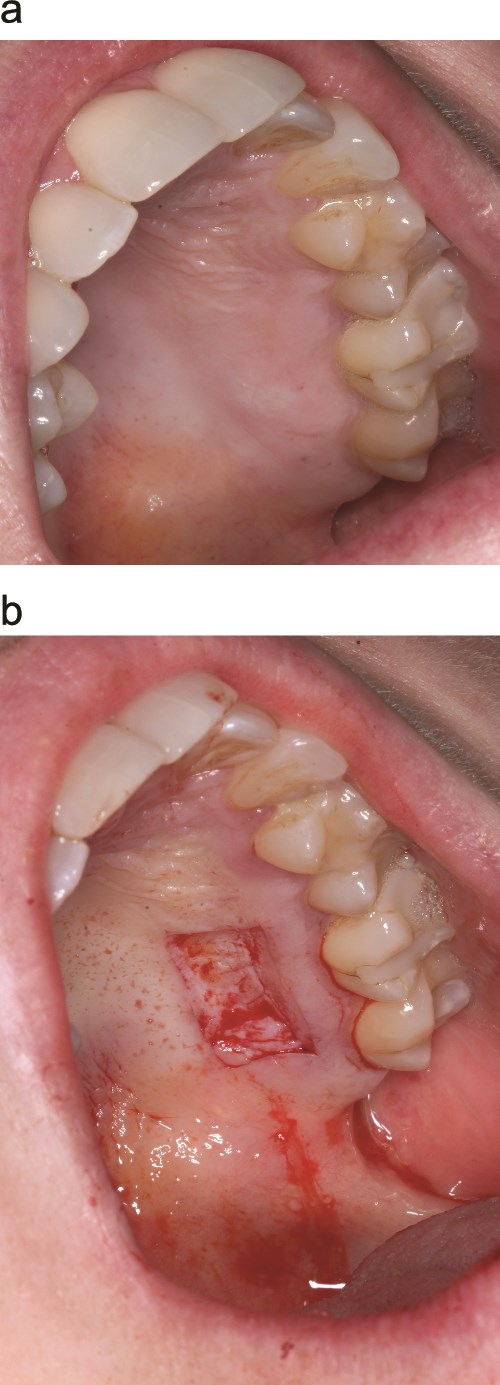

Consecutive patients indicated for STAP who had not previously undergone a STAP but were treatment-planned for potential staged procedures were invited and provided written informed consent. Palatal grafts were harvested with dimensions <20 mm in length and < 2 mm in thickness (Fig. 1a and b). The first 12 patients receiving STAP in three private periodontal practices were managed with the sandwich dressing technique. All procedures were performed by a periodontist on patients with ASA 1 or 2 and 2 patients had comorbidities.

Palatal harvest site (a) palatal wound immediately after graft removal (b).